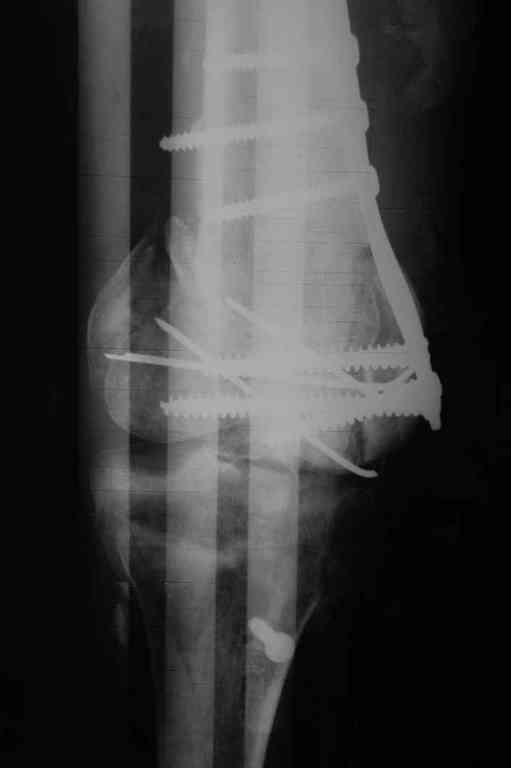

Re: Последствия открытого перелома дистального отдела бедра

Коллеги фиксатор Numelock II